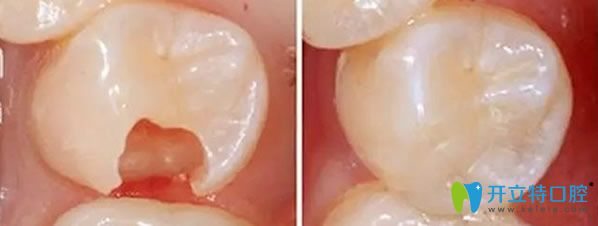

嵌體修復(fù)效果對比圖

嵌體的優(yōu)勢,比傳統(tǒng)補牙要精細(xì),醫(yī)生在制作嵌體的時候,會控制它與牙體的彌合程度,盡可能的避免了牙齒在日后的使用中再次出現(xiàn)齲壞??梢曰謴?fù)原來牙齒的外形,增加牙齒的咀嚼功能。